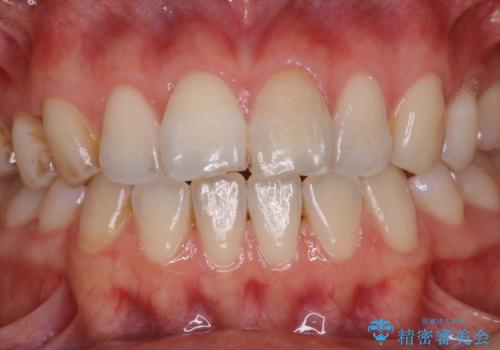

1年ぶりにPMTCで歯の着色落とし

- しばらく歯科医院へ行けなかったため、しっかり着色や汚れを落として欲しいとのことで来院されました。全体的に着色や歯石が付着していたためPMTC60分コースを行いました。